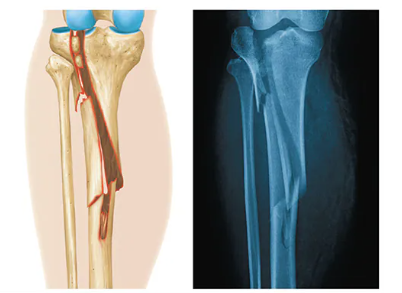

Spiral